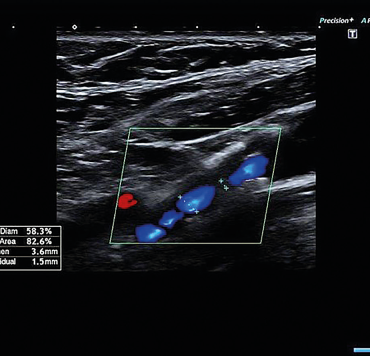

Obr. 3 Duplexní sonografie s obrazem symptomatické stenózy pravé ACI 80–85 % ACI – arteria carotis internaDruhý den po přijetí byl pacient přeložen na Neurochirurgickou kliniku KZ, a.s. – Masarykova nemocnice v Ústí nad Labem. V regionální anestezii byla provedena endarterektomie odstupu pravé ACI. Výkon proběhl bez komplikací a pacient byl třetí pooperační den propuštěn do domácí péče. Kon­trolní duplexní sonografická vyšetření provedená v naší neurosonologické laboratoři v průběhu tří, šesti a 12 měsíců po operaci prokázala normální průtok v ACI, bez známek restenózy. Při půlroční i roční klinické kontrole byl pacient bez potíží, bez recidivy amaurosis fugax či jiné TIA nebo iCMP.

Obr. 4 Symptomatická stenóza pravé ACI 80–85 % ACI – arteria carotis internaNeodkladně provedená klinická a zobrazovací vyšetření u pacientů s amaurosis fugax jsou zásadní pro zjištění její etiologie a nastavení sekundární prevence cerebrovaskulárních příhod. Důležité je vyšetření magistrálních mozkových tepen. Přítomnost symptomatické intrakraniální nebo extrakraniální okluze či stenózy > 50 % je podle studie CATCH nejvýznamnějším prediktorem jak pro recidivu amaurosis fugax nebo retinálního infarktu, tak především pro mozkový infarkt. Karotická endarterektomie je podle současných klinických doporučení zlatým standardem v léčbě symptomatické stenózy ACI. CEA je indikována u pacientů se 70–99% symptomatickou stenózou ACI, kterým přináší nejvýznamnější klinický přínos s absolutním snížením rizika iCMP o 16 % v průběhu následujících pěti let. Operace by měla být provedena optimálně během dvou týdnů od amaurosis fugax (2.–14. den). Čím dříve je CEA provedena, tím významnější je redukce rizika recidivy iCMP. Před provedením, v průběhu a po CEA by neměly být vysazeny ASA a statin. Věk není absolutní kontraindikací, z CEA profitují i pacienti starší 75 let, pokud nemají závažné srdeční či jiné limitující onemocnění. U pacientů se symptomatickou stenózou ACI 50–69 % může být CEA zvážena v případě, že bude provedena na pracovišti s nízkým rizikem perioperační morbidity a mortality (< 3 %), ale profit z výkonu je menší (absolutní redukce rizika o 4,6 %). Benefit CEA u pacientů s < 50% stenózou ACI nebyl prokázán.